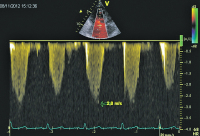

CW-Doppler

Abbildung 6: CW-Doppler der Trikuspidalinsuffizienz. Anhand der Geschwindigkeit errechnet sich ein systolischer pulmonalarterieller Druck von 40–45 mmHg.